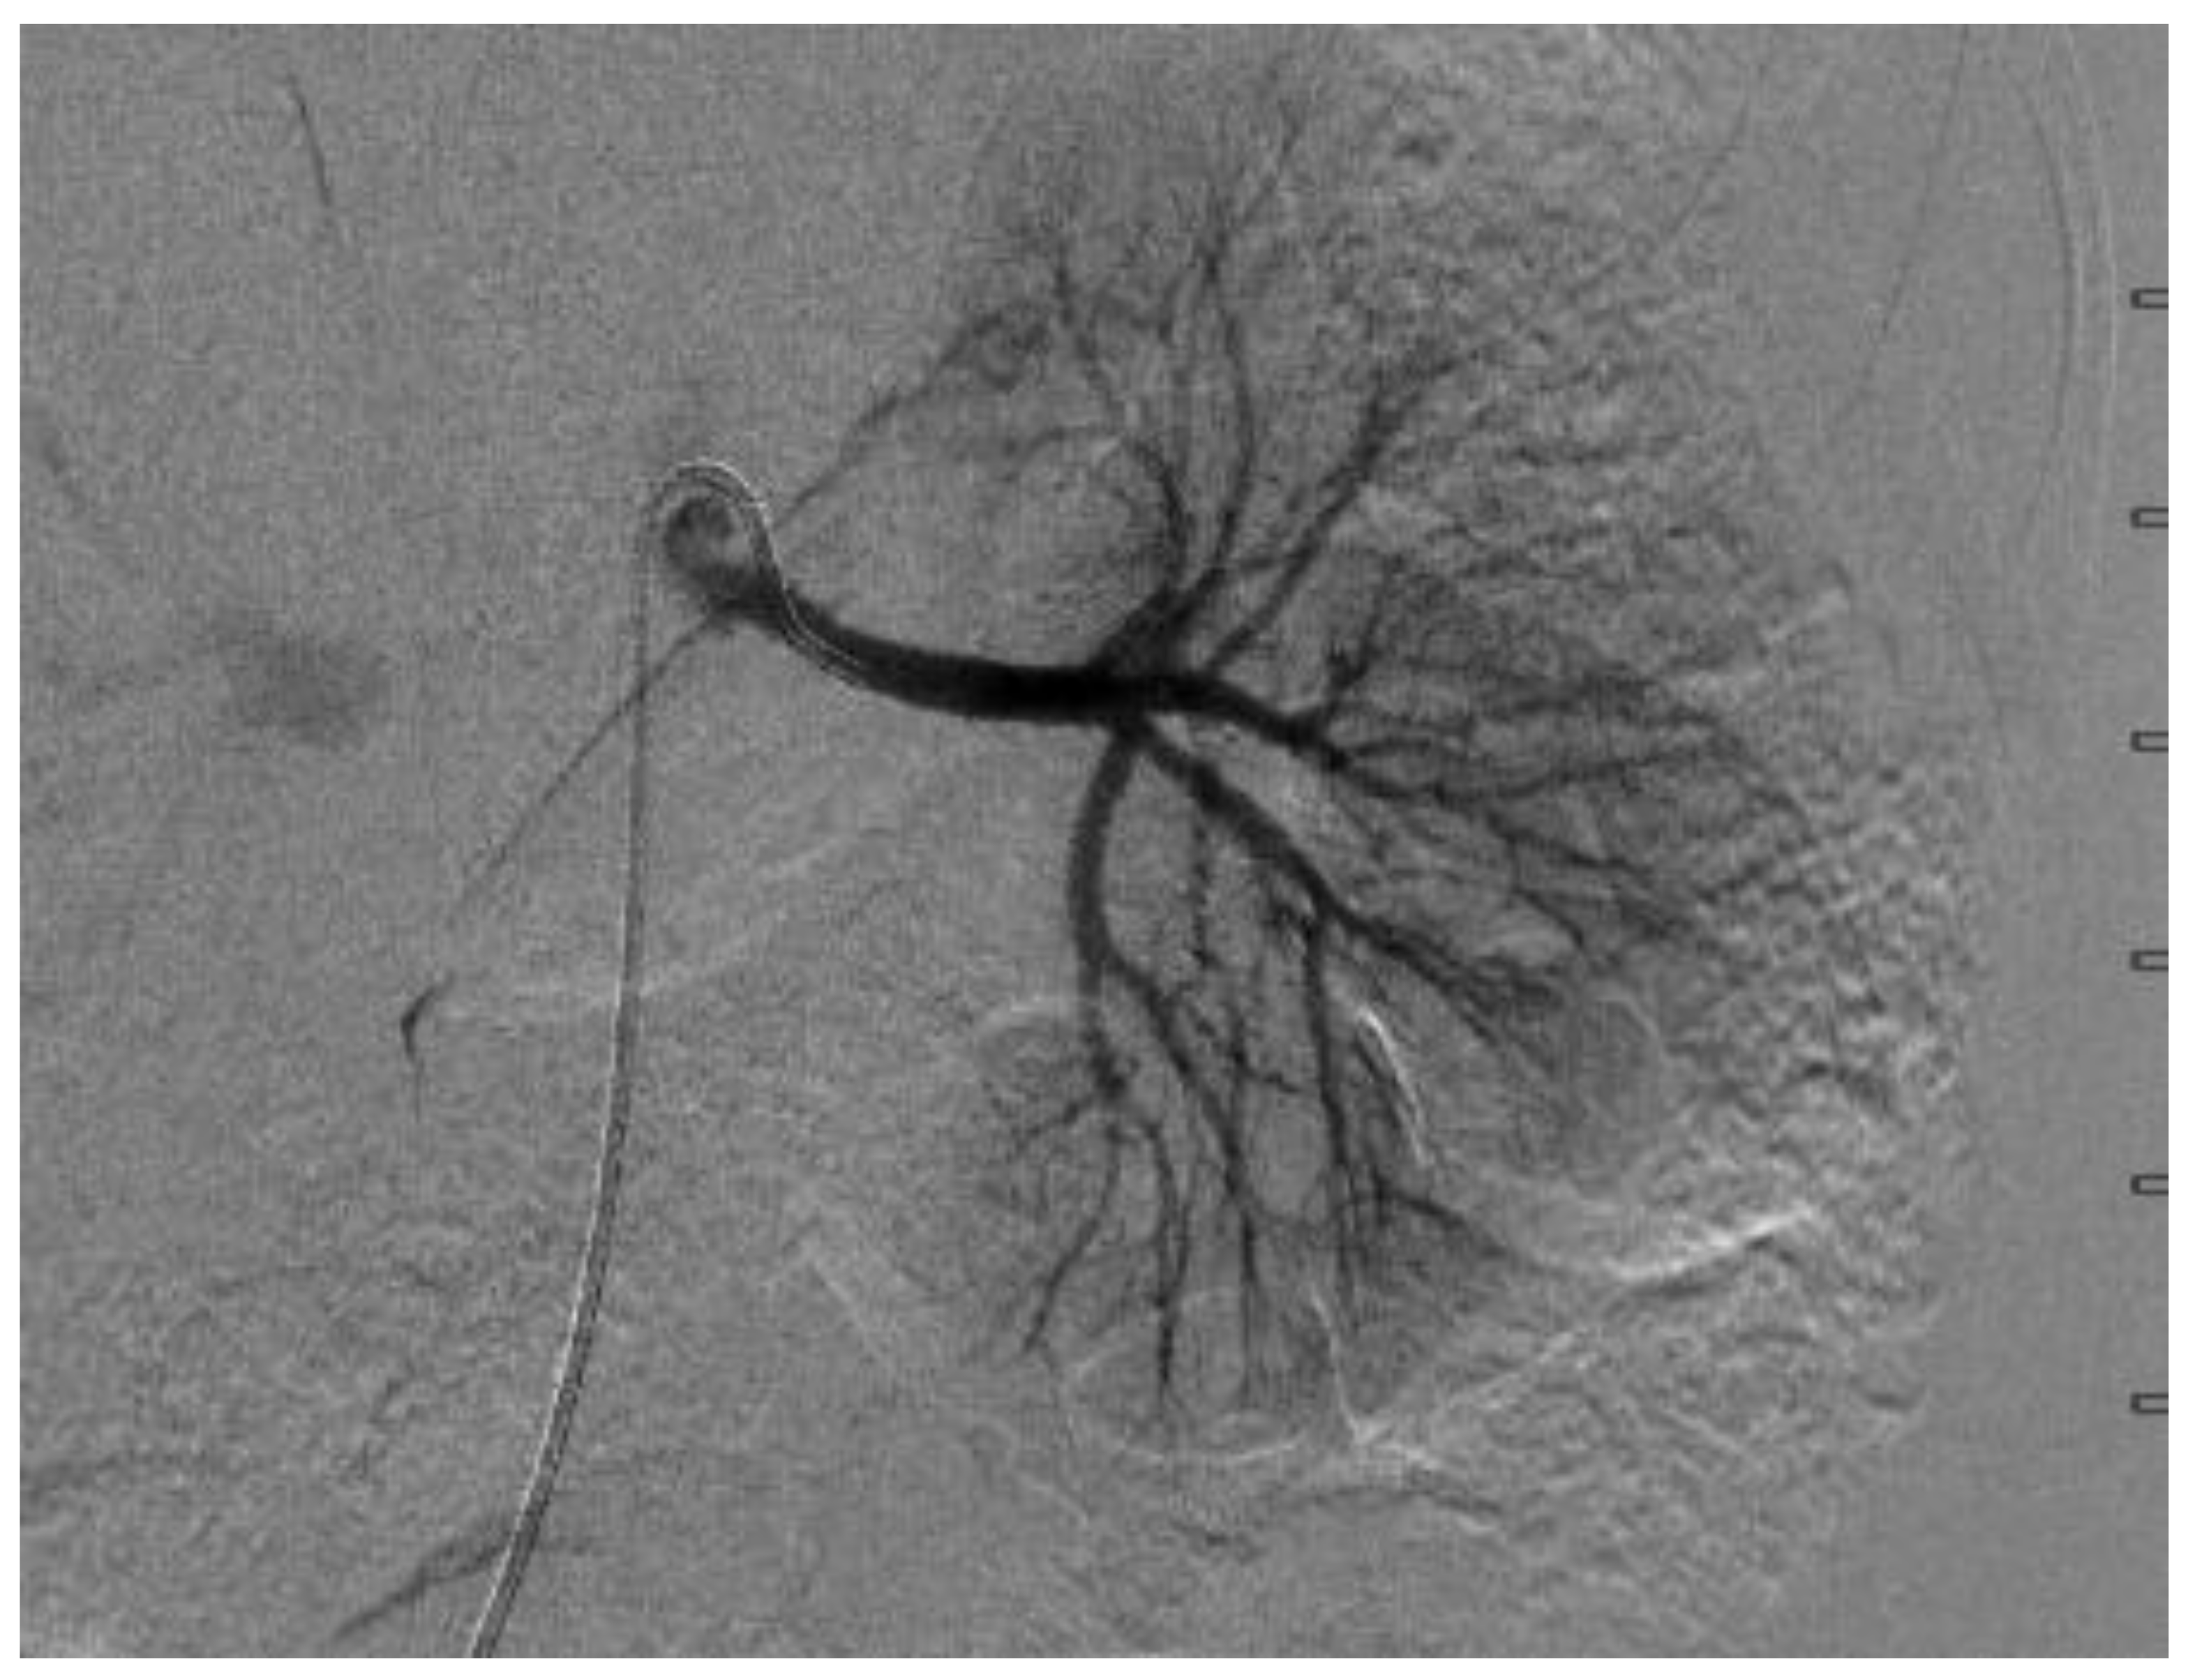

A few days later, she underwent a digital subtraction angiogram (DSA), which showed a beaded appearance of the right proximal main RA, which caused a focal stenosis with post-stenotic dilatation (Figure 3 and Figure 4). The pressure gradient across the stenotic lesion was 40 mm Hg. There was normal renal parenchymal perfusion. The left RA demonstrated a normal appearance of the main and branch arteries with normal renal parenchymal perfusion and no evidence of stenosis and irregularity. A diagnosis of right RA stenosis, most likely due to focal FMD, was made. In conjunction with vascular surgery and intervention radiology, it was collectively decided not to pursue the intervention of the stenotic lesion due to the risk of complication, specifically the injury or dissection of the right RA, especially because her BPs were relatively controlled on five antihypertensive agents. Subsequent to the angiogram, enalapril was added once bilateral RA stenosis was excluded for optimal BP control. A CTA of the head and neck vessels to look for evidence of FMD in the head and neck showed a normal vasculature of the vessels. Baby aspirin was started to prevent thromboembolic events.

Figure 3.

Digital subtraction angiography of the right renal artery, which showed proximal renal artery stenosis.